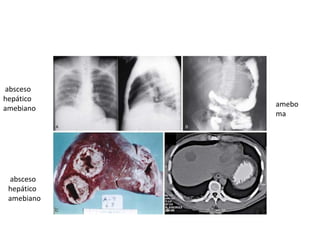

absceso

hepático

amebiano

amebo

ma